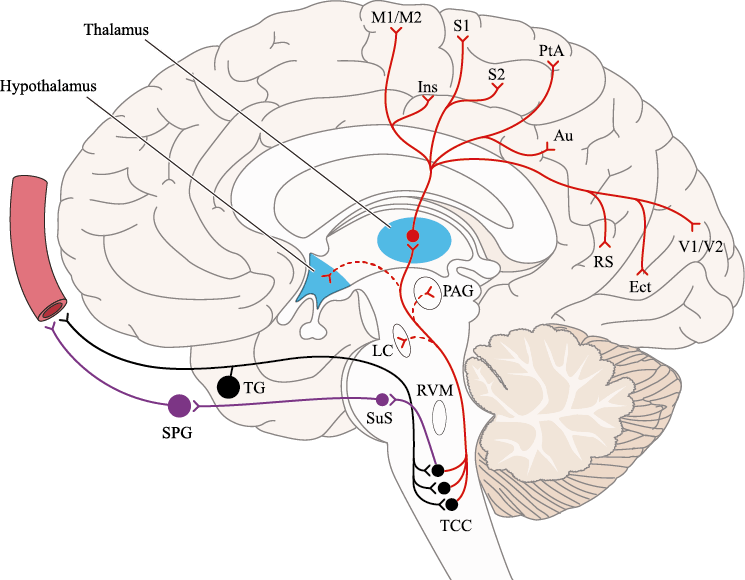

Un principio importante de esta teoría es que el desencadenante principal de la migraña proviene de la periferia, en los vasos sanguíneos de la duramadre, con la activación del sistema trigeminovascular proveniente del disparo de las neuronas trigeminales periféricas de primer orden en respuesta a una lesión nociceptiva o señales provenientes de las meninges que liberan mediadores neuroinflamatorios. La activación sostenida de las neuronas nociceptivas meníngeas durales provoca la activación secuencial y la sensibilización de las neuronas trigeminovasculares de primer orden (nociceptores periféricos), segundo orden (a nivel del TCC-complejo trigémino cervical) y tercer orden (trigeminotalámico), (Figura 5) así como la activación ascendente del cerebro, tallo y otras estructuras diencefálicas(97).

El dolor de la migraña es, sin duda, una consecuencia de la activación o la percepción de la activación de los mecanismos neurovasculares, de allí que sea considerado un trastorno puramente neuronal. Mucha evidencia indica que los cerebros de las personas con migraña pueden ser diferentes en la forma en la cual responden a la estimulación sensorial, incluso interictalmente(102). Una hipótesis alternativa y que lo abarca todo es que el cerebro está en el centro del desencadenamiento de la migraña. Más que una activación secuencial de diferentes regiones del cerebro, la migraña es un trastorno del cerebro y por lo tanto, se considera un “estado cerebral”, que es una consecuencia de cambios o disfunciones en las regiones del tronco encefálico y el hipotálamo, que contribuyen a su vez a cambios a nivel celular y vascular en muchas regiones del cerebro. Esta hipótesis establece que la migraña puede describirse mejor como una consecuencia de la disfunción en el tronco encefálico y los núcleos hipotalámicos que normalmente modulan o activan las entradas sensoriales, como el tacto, la luz, los sonidos y los olores. Estos núcleos del tronco encefálico y del hipotálamo pueden considerarse “mediadores de la migraña” y su disfunción puede llevar al fracaso de los mecanismos de integración y filtrado cerebrales, lo que da como resultado la percepción de activación de los sistemas sensoriales en condiciones normales. La compleja red de conexiones entre las regiones del tronco encefálico, que incluyen PAG, RVM, locus ceruleus y SuS y los núcleos diencefálicos, incluidos el hipotálamo, el tálamo y la corteza, pueden conducir a la generación de síntomas a través de la misma disfunción central. La disfunción en estas regiones, a través del control descendente del tráfico nociceptivo trigeminovascular, puede conducir a la percepción del dolor de cabeza a través de la palpitación de los vasos normales y la disfunción continua puede conducir a la sensibilización central de las neuronas trigeminovasculares y la exacerbación del dolor con la actividad física normal, así como en la piel: alodinia cefálica y extracefálica. La convergencia de entradas sensoriales en el tálamo que se proyectan a la corteza puede explicar la hipersensibilidad a la luz, los sonidos y los olores. La misma disfunción puede conducir a cambios homeostáticos, controlados por el hipotálamo, relacionados con el sueño, la alimentación y la actividad. La alteración general de la función cortical y subcortical puede desencadenar eventos como el aura migrañosa y extenderse a una incapacidad general para funcionar correctamente. Los factores genéticos heredados juegan claramente un papel en la predisposición a la susceptibilidad a la migraña, al igual que el papel de los desencadenantes potenciales de la migraña, cuyo vínculo común parece jugar en el corazón de la homeostasis cerebral en el hipotálamo y el tronco encefálico. (figura 7).

La relevancia del tronco encefálico para la fisiopatología de la migraña está respaldada por estudios clínicos e investigaciones básicas. En presencia de la crisis dolorosa, se ha demostrado que hubo un aumento del flujo sanguíneo cerebral en el mesencéfalo, la protuberancia rostral dorsal cerca del PAG y los núcleos del rafe(22) y además se localizaron varios síntomas de migraña en diferentes áreas del cerebro concomitantemente con la experiencia de dolor de cabeza en la corteza cingulada, fotofobia en la corteza de asociación visual y fonofobia en el auditivo, corteza de asociación. Estas señales desaparecieron después de la terminación exitosa del ataque. Sin embargo, el aumento de flujo sanguíneo cerebral en el tronco encefálico persistió en la fase temprana sin dolor. Por lo tanto, esta estructura refleja no solo un síntoma de migraña, sino que también indica una disfunción de importancia para la generación o el mantenimiento del ataque de migraña en sí.

El procesamiento del dolor es complejo y está mediado por una red de estructuras neuronales que incluyen la corteza cingulada, las ínsulas y el tálamo(28). El tálamo está en el corazón del procesamiento central y la integración de la información nociceptiva y se considera un centro de retransmisión para manejar la información sensorial entrante e incluso modularla. Se cree que la llamada “matriz del dolor”, que incluye el tálamo, así como las áreas somatosensoriales primarias (S1) y secundarias (S2), la corteza cingulada anterior (CCA) y la corteza prefrontal, está involucrada en la integración de todos los sentidos, respuestas afectivas y cognitivas al dolor y se activan durante el procesamiento nociceptivo(28). (Figura 18)

Siendo el tálamo el centro principal para el procesamiento de la información nociceptiva sensorial en el cerebro, la transmisión de esta información para su procesamiento en las estructuras corticales donde los individuos la perciben es un factor clave. (Figura 18) Los tratamientos agudos como los “triptanos” (agonistas de los receptores 5-HT1B/1D)(29) y los antagonistas de los receptores CGRP(30) pueden inhibir las entradas nociceptivas durales agudas. Del mismo modo, los preventivos de la migraña propranolol(31), valproato de sodio(32) y topiramato(33)también pueden inhibir las entradas trigeminotalámicas nociceptivas durales en el VPM (Núcleo ventral posteromedial).

La evidencia de la activación talámica durante la migraña es clara(34) y su papel va más allá del mero relevo en el procesamiento de información nociceptiva sensorial a las cortezas somatosensoriales.

Muchos pacientes también describen la privación del sueño o el sueño interrumpido o reducido continuamente, como un posible desencadenante de la migraña(50). La regulación del sueño, particularmente dentro del hipotálamo, está fuertemente ligada al desencadenamiento de la migraña. Los núcleos del mesencéfalo están involucrados al desencadenamiento de la migraña, además de contribuir a los síntomas asociados a través de proyecciones al hipotálamo y otros núcleos del tronco encefálico y diencefálico. Además de controlar la modulación del dolor, las cé- lulas “ON: ENCENDIDAS” y “Off: APAGADAS” en RVM (médula medial rostro-ventral) y NRM (nú- cleos del rafe magno) (Figura 21).

También están involucradas en el control de respuestas a estímulos externos inocuos, actividad motora y procesos homeostáticos(51). Las células “On: ENCENDIDAS” están activas dependiendo del estado durante las horas de vigilia, pero no durante la alimentación y la micción, o durante el sueño, mientras que las células “Off: APAGADAS” están activas durante el sueño y activas durante la vigilia solo antes de micción, así como durante la alimentación. Por lo tanto, la activación de células “Off: APAGADAS”, durante el sueño, la alimentación y la micción, evita que respondan a estímulos inocuos e incluso nocivos agudos, mientras que durante la vigilia la activación de células “On: ENCENDIDAS” facilita el estado de alerta a los estímulos sensoriales. Además, la vlPAG (Área ventrolateral de la sustancia gris periacueductal) (Figura 22) participa en los mecanismos de excitación, a través de la activación de las neuronas dopaminérgicas durante la vigilia y la inactivación de estas neuronas durante el sueño. En el contexto de los posibles desencadenantes de la migraña, la privación del sueño es un proceso homeostático que da como resultado respuestas neuronales específicas en la vía PAG-RVM, en particular, la activación de las células “ON” y la inhibición de la activación de las células “OFF”.

La activación del sistema trigeminovascular da como resultado la liberación de varios neuropéptidos basados en las inervaciones simpática, parasimpática y sensorial de la vasculatura craneal, que se resumen en la figura 23.

La inervación simpática se caracteriza por NPY y norepinefrina(52), ambos de los cuales son vasoconstrictores, mientras que las fibras parasimpáticas se caracterizan por VIP y PACAP, que se encuentran entre los vasodilatadores más potentes(24).

Las inervaciones sensoriales se caracterizan por la sustancia P, CGRP y PACAP (53).